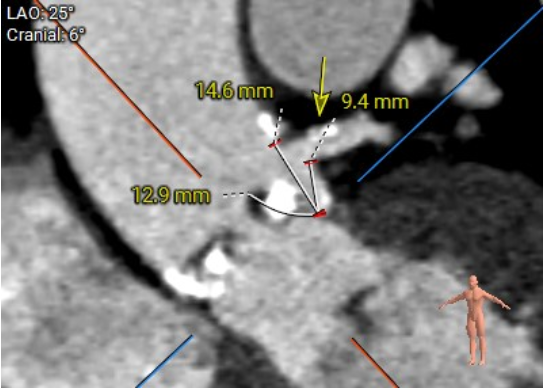

植入视图:

该患者瓣环最小径22.4mm,且瓣叶重度钙化,此外左无冠窦之间有一处柱状钙化延伸至LVOT,决定术中用20mm球囊预扩,评估冠脉风险和指导瓣膜选型。此外,患者双侧瓣叶长度均大于冠脉高度,且左冠团状钙化,冠脉遮挡高危,拟在TAVR前行左冠支架保护。

当猪尾位于无冠窦窦底,初始释放位置通常令显影环处于猪尾中部,由于患者根部存在较重钙化,猪尾无法到达窦底,因此递送显影环适当参照猪尾中部以下的位置:

切换至左前斜评估左冠窦瓣膜深度,位置在0位甚至略高于0位,整体位置偏高,Evolut PRO推荐标准植入深度为环下3mm,因此需要回收调整位置: